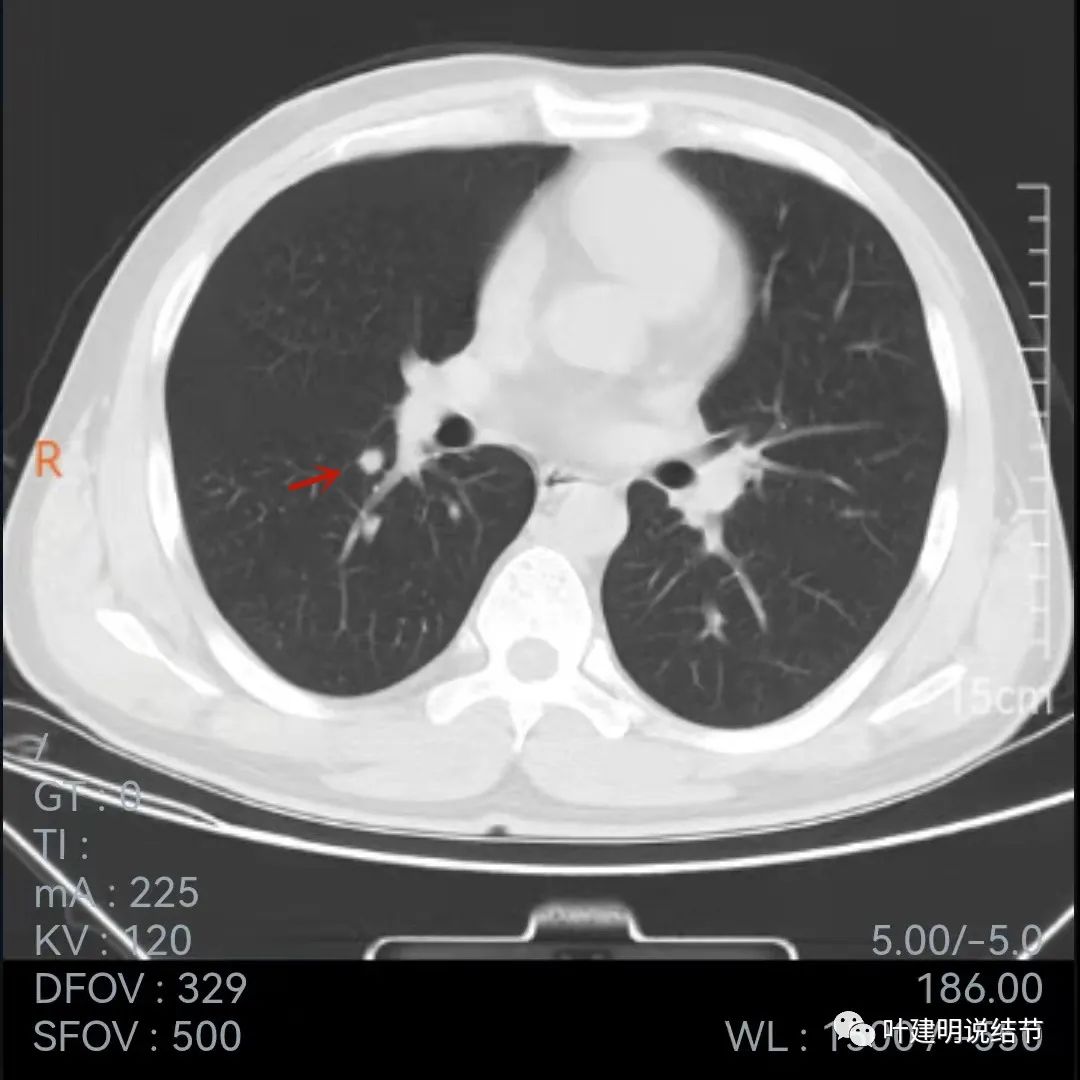

再看下面2020年7月的平扫片子:

非薄层的看,病灶还是小结节,实性,边缘似乎比前一年略有毛糙,胸膜轻微牵拉,黄色箭头所指似乎病灶中央的密度比周围部分略低,会不会是肉芽肿性炎伴有少许坏死?